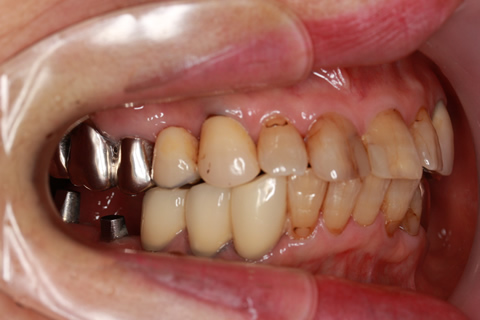

• 症例2

治療前

インプラント埋入時

治療後

年齢・性別

57歳男性

治療期間

3ヶ月

抜歯

なし

治療費

154万円

備考

左上5.6.7 及び左下6.7欠損

治療内容

左上5.6.7と左下6.7欠損部にインプラント埋入

施術の副作用(リスク)

オペによる知覚障害。インプラントによる歯肉炎。インプラント脱落。